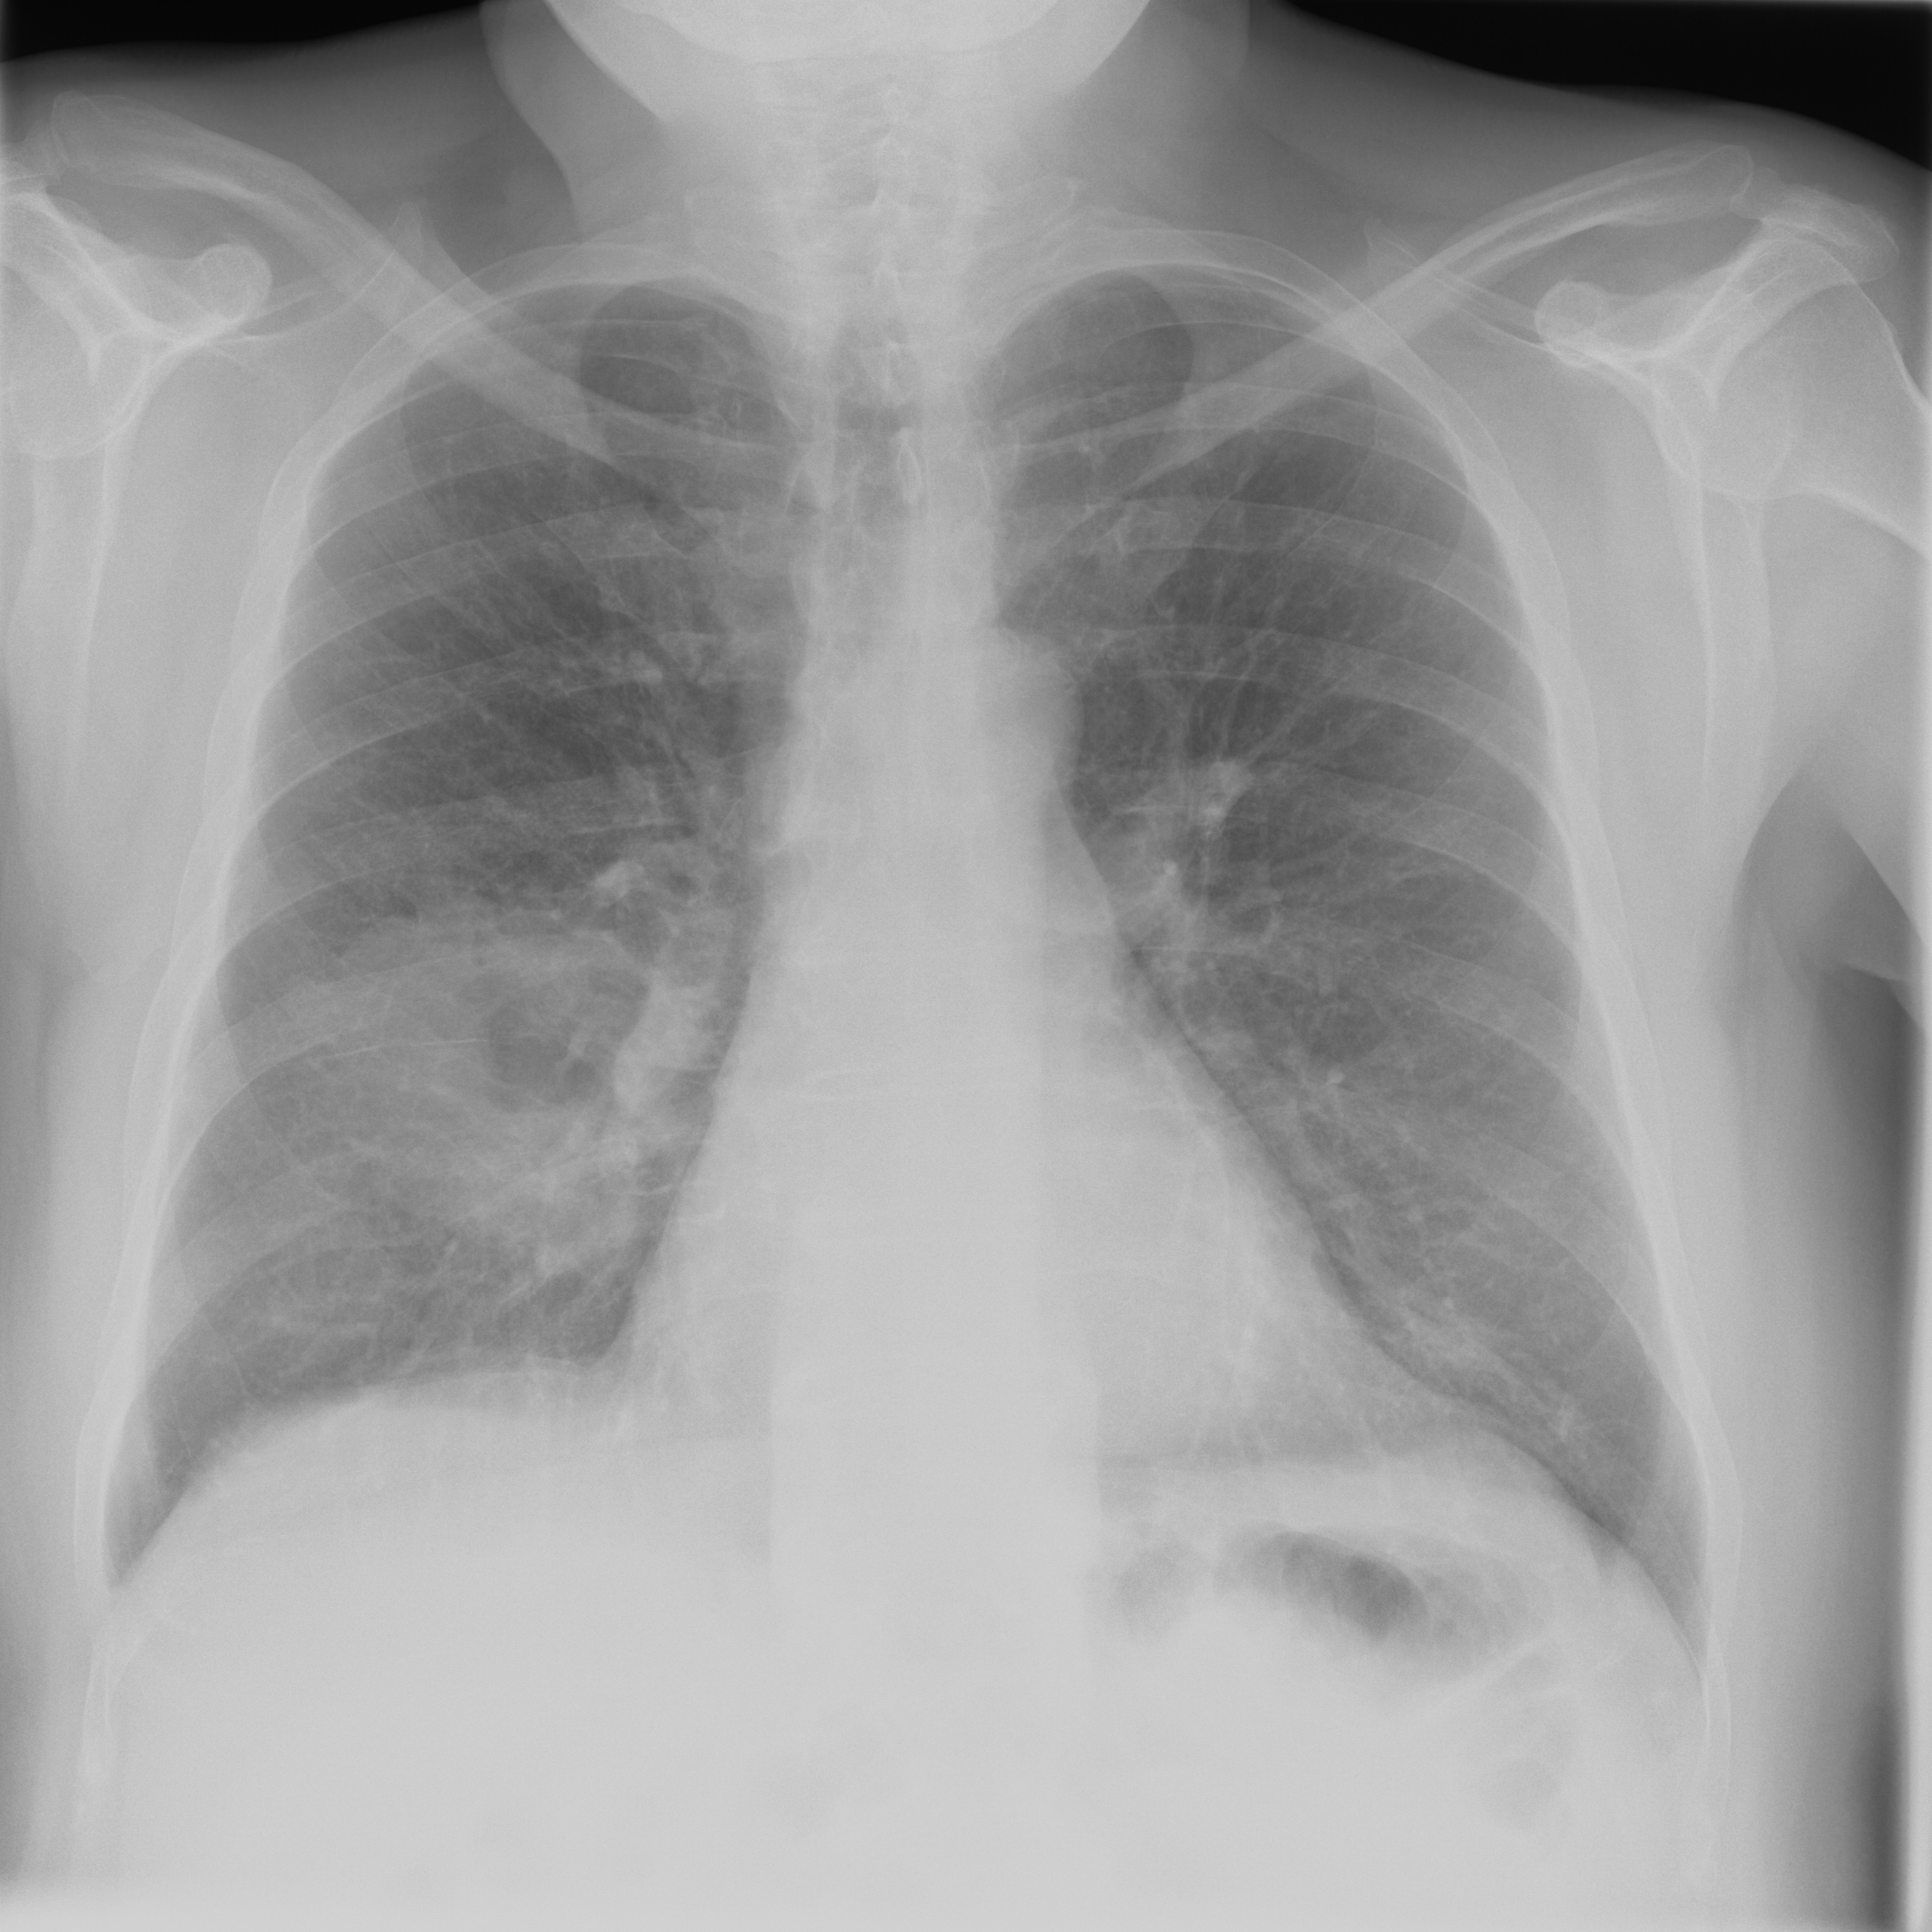

3.3.2 Data

Posteroanterior chest radiographs were acquired on two imaging systems (both Discovery XR656 HD models, GE Healthcare, USA) at Cambridge University Hospitals NHS Trust. Each scanner was being set up in the hospital with different post-processing parameters (chosen by the operating radiologists), which are used here as reference images, see Figure 7 and 8(a). Additional images, serving as real-life examples of lower quality, were produced for each radiographic exposure using multiple different post-processing settings. The post-processing was applied in the hospital directly on the scanner itself by adjusting parameters in the provided framework.

Refer to caption

(a) Reference

(b) (22.8, 0.97, 0.08)

(c) (21.2, 0.96, 0.07)

Figure 8: Chest X-Ray scans with different kinds of post-processing; (a) serves as reference, (b) is wrongly judged as better visualization by PSNR and SSIM, LPIPS gives a slightly worse evaluation for (b).

FR-IQA mismatches

In Figure 7, contrast deviation and edge enhancement were reduced in (b), but increased in (c), the noise reduction algorithm was removed in both. The brightness was increased in both images but more so in (c) and low-contrast enhancement was removed in (b). The result is that (b) has relatively low contrast in the lungs compared to the reference (a) and radiograph (c). In Figure 8, edge enhancement has been dramatically increased in (b), whilst the contrast deviation and tissue contrast have been reduced. In (c), the brightness, tissue contrast and edge enhancement have been slightly increased. Consequently, (b) provides low contrast in the lungs with excessively prominent lung markings and vasculature which make it harder to detect abnormalities such as a pneumonia.

All of the chosen FR-IQA metrics wrongly judge (b) as the better image in the first example Figure 7, and the results in (b) and (c) of the second example Figure 8 are quite close, where PSNR and SSIM are also providing the wrong order. The tested measures are not suitable to evaluate the quality of data sets with X-Ray images that have large variations regarding contrast, luminance and sharpness.